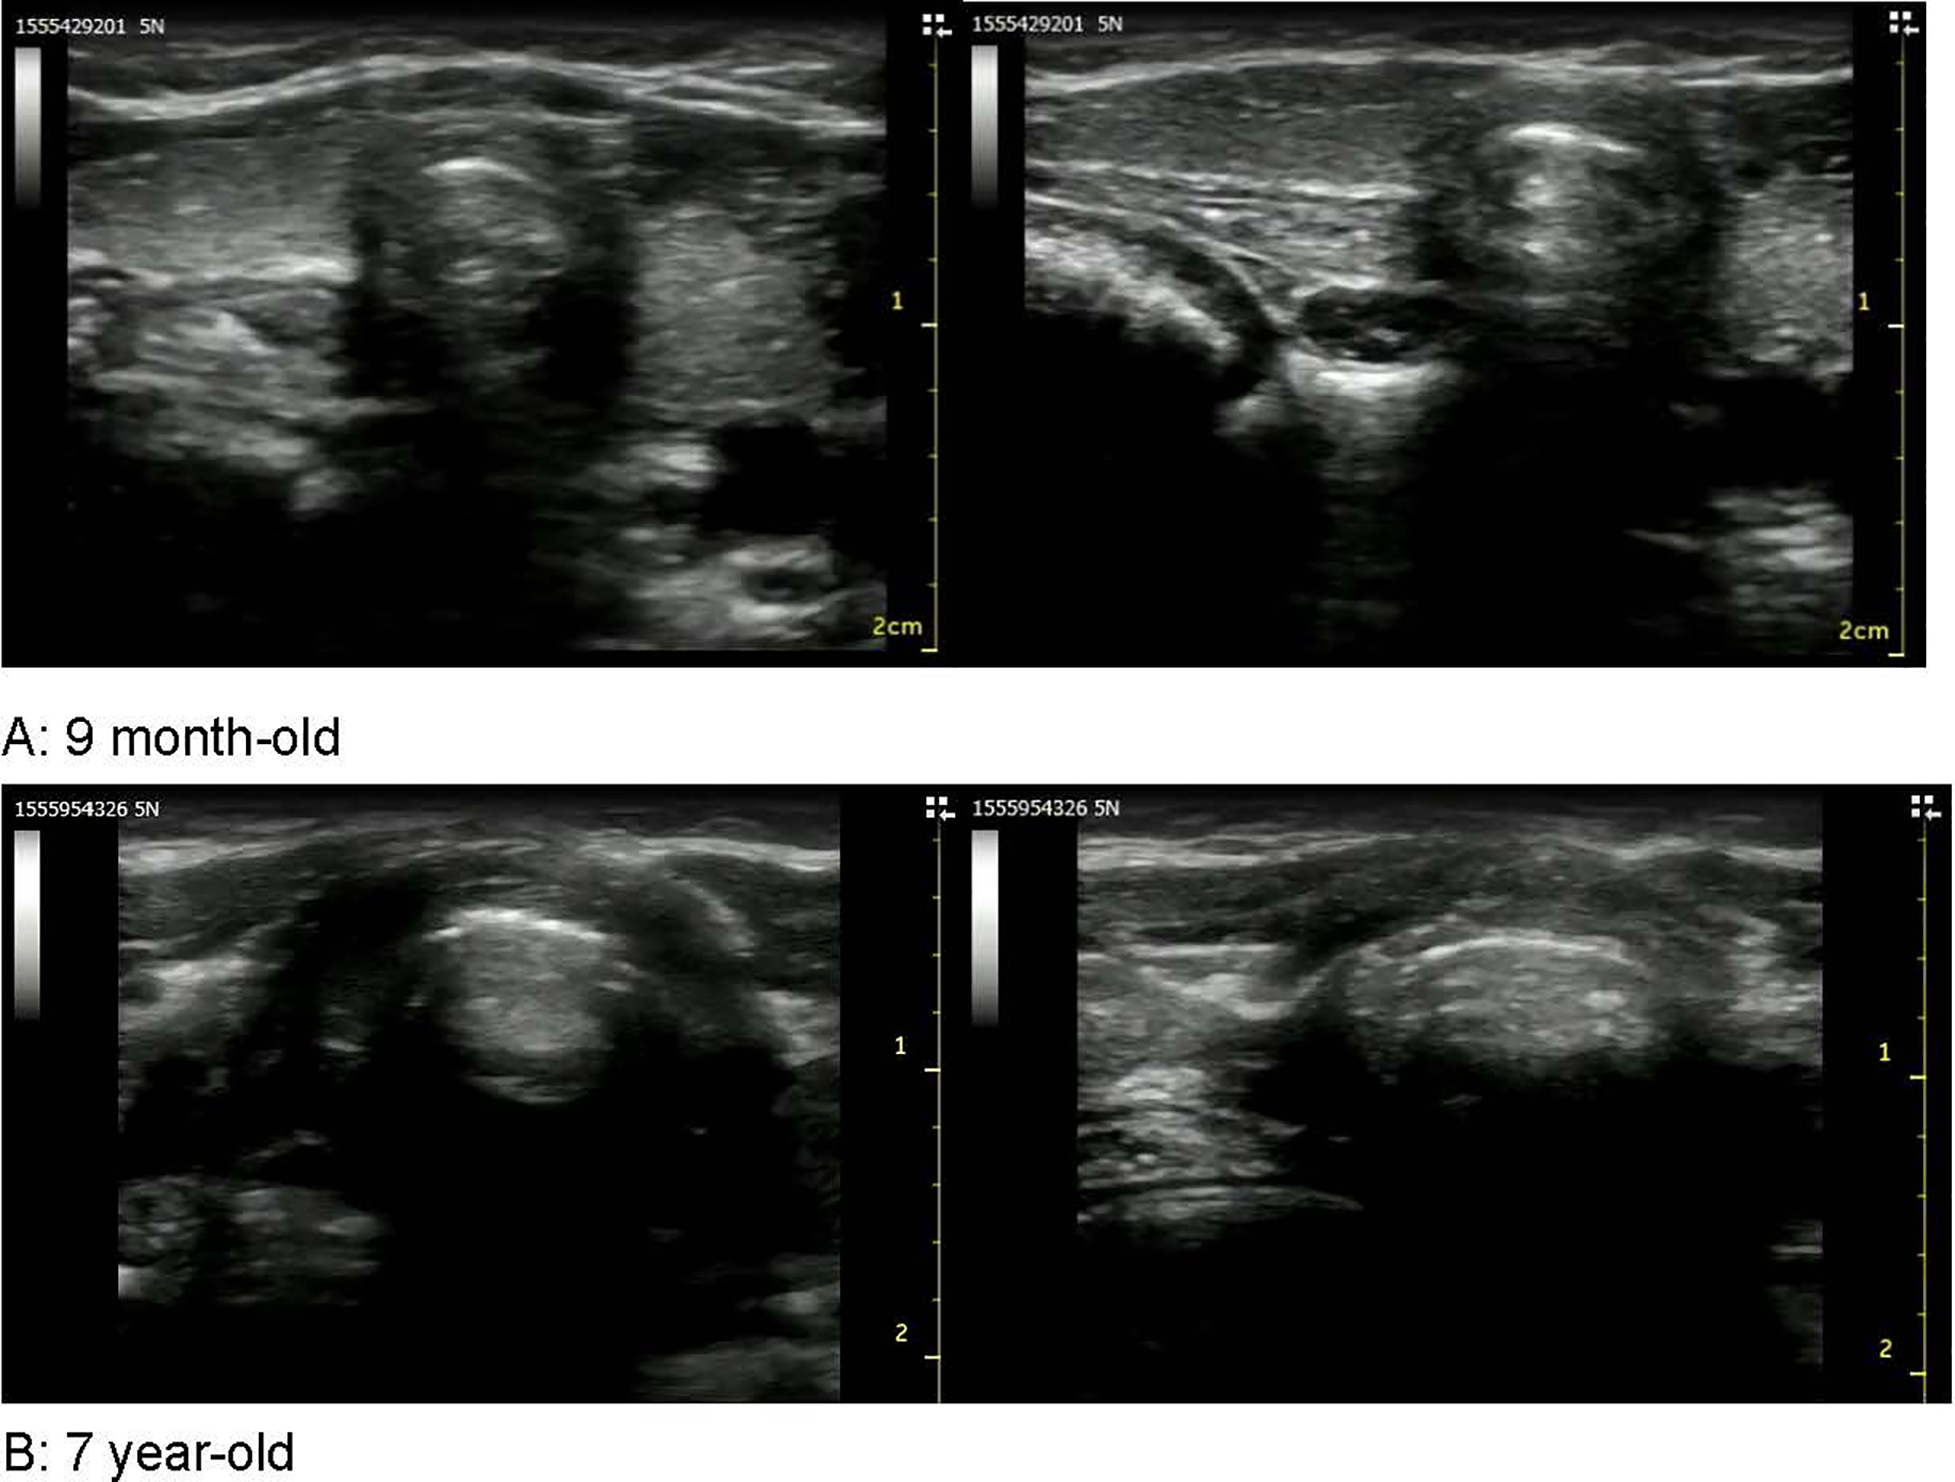

Altogether, 24 patients were included in this study. Four children were excluded because their patients did not provide informed consent. Therefore, a total of 20 patients were included in the analysis. No adverse events occurred during the study. The patients’ characteristics are shown in Table 1. The median deviations of the cricothyroid membrane from the midline divided by the tracheal diameter were 0.16 ± 0.09, 0.05 ± 0.04, 0.04 ± 0.04, and 0.02 ± 0.03 in groups 1, 2, 3, and 4, respectively (Table 2). A significant difference was noted between group 1 and groups 3 and 4. However, no statistical difference was noted between groups 1 and 2 (Table 3). A p-value was 0.053. The 9-month-old baby in group 1 showed the migration of the cricothyroid membrane while the 7-year-old boy in group 3, showed less migration and more compression (Figure 2). Figure 3 shows that the deviation of the cricothyroid membrane divided by the tracheal diameter decreased with increasing age.

Figure 2. Images of the cricothyroid membrane. These images showed the cricothyroid membranes of a 9-month-old (A) and a 7-year-old (B). The 9-month-old showed the migration of the cricothyroid membrane while the 7-year-old showed less migration and more compression.